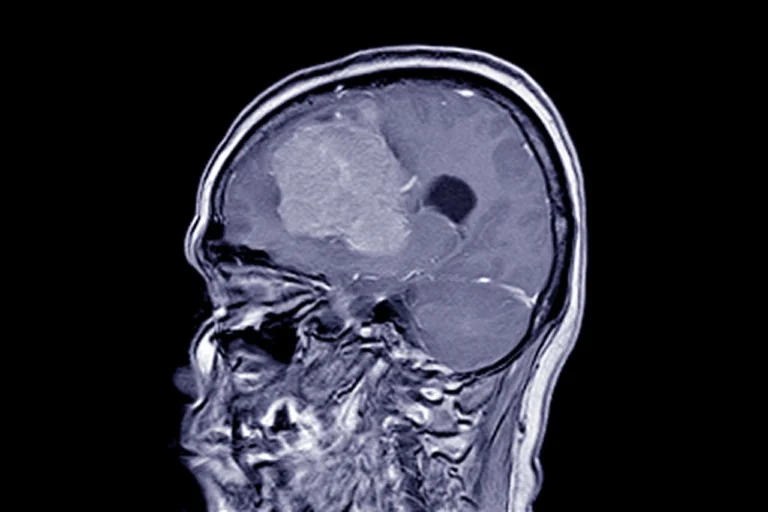

Менінгіома — це одна з найпоширеніших пухлин головного мозку,...